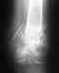

Здравствуйте,Хотел бы получить консультацию специалистов. У мне был перелом правого бедра, был установлен штифт внутри бедренной кости.

Скажите, пожалуйста, необходимо ли его удалить после сращения?Спасибо